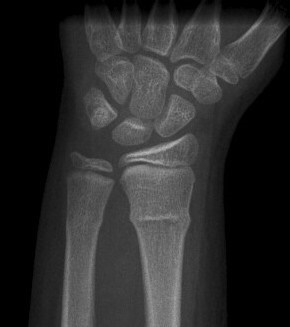

is incorrect. This type of fracture is usually caused by a compression force. This would create a 'buckle' as if the bone was 'shortened'. This is can be very commonly missed due to the subtle deformity it causes. It usually causes buckling of one side but if the compression is strong enough it can cause more severe deformity.

Buckle (torus) fracture - e Image used on license from Radiopaedia